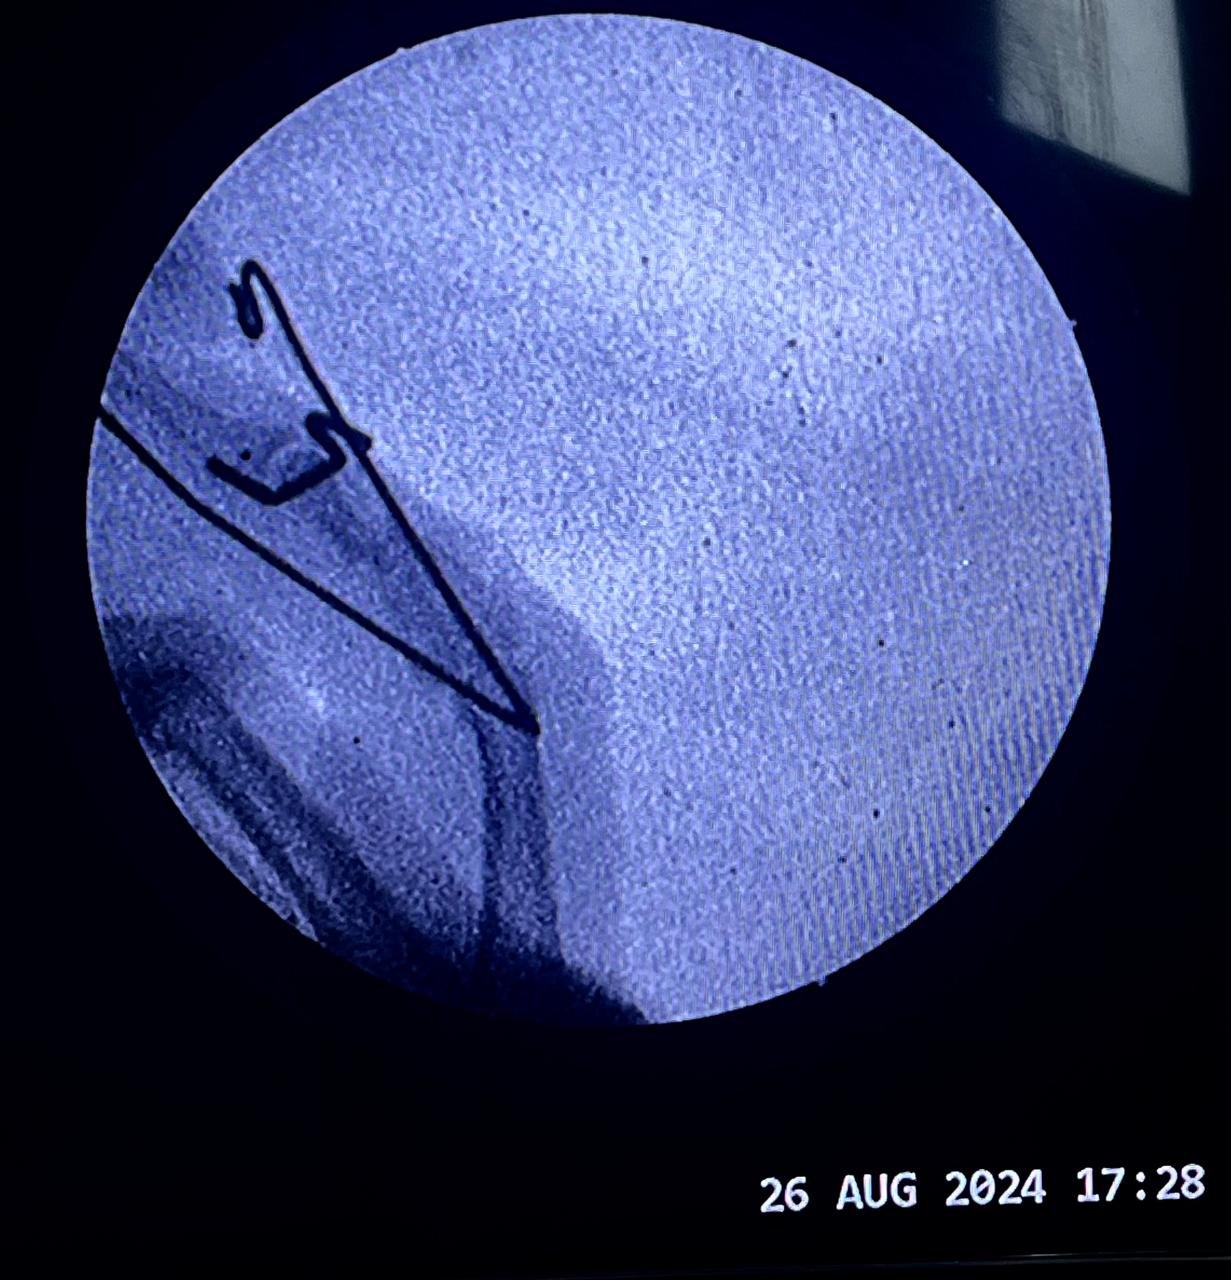

Non union with Broken DCS implant & revision

correction surgery